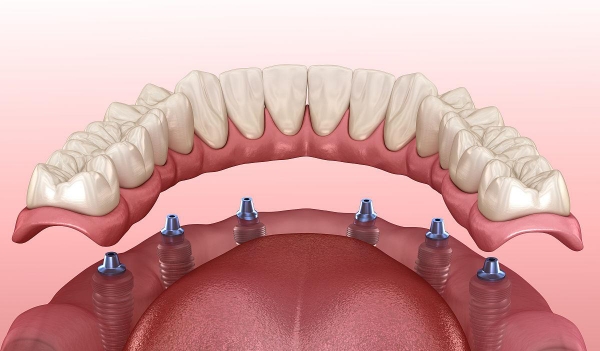

如果你缺了半口或全口牙,數(shù)字化種植的優(yōu)勢(shì)較大。傳統(tǒng)種牙需要種很多顆,手術(shù)時(shí)間長、創(chuàng)傷大。而數(shù)字化種植可以用更少的種植體支撐整排假牙,比如All-on-4技術(shù),只需要種4顆種植體就能支撐半口假牙。